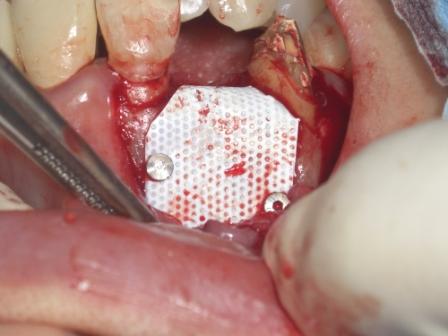

昨日のオペの報告です。かなり難しいケースでした。頬側、そして一部口蓋側の骨までもが吸収していました。

それに着けて審美要素が大きい前歯部で方向性のコントロールが難しかったです

両隣在歯を結んだラインの約2ミリ内側

これにより補てん剤を充填してGBRを行えば頬側側にかなりの骨ができます。

右上1番の骨と右上3番のcejを結んだラインから約4ミリ根尖側へ・・・これによりアストラの利点であるインプラント上への骨造成を行いより確実な歯肉のサポートを行います。

そして最後にGBRトCTGを行い終了です。